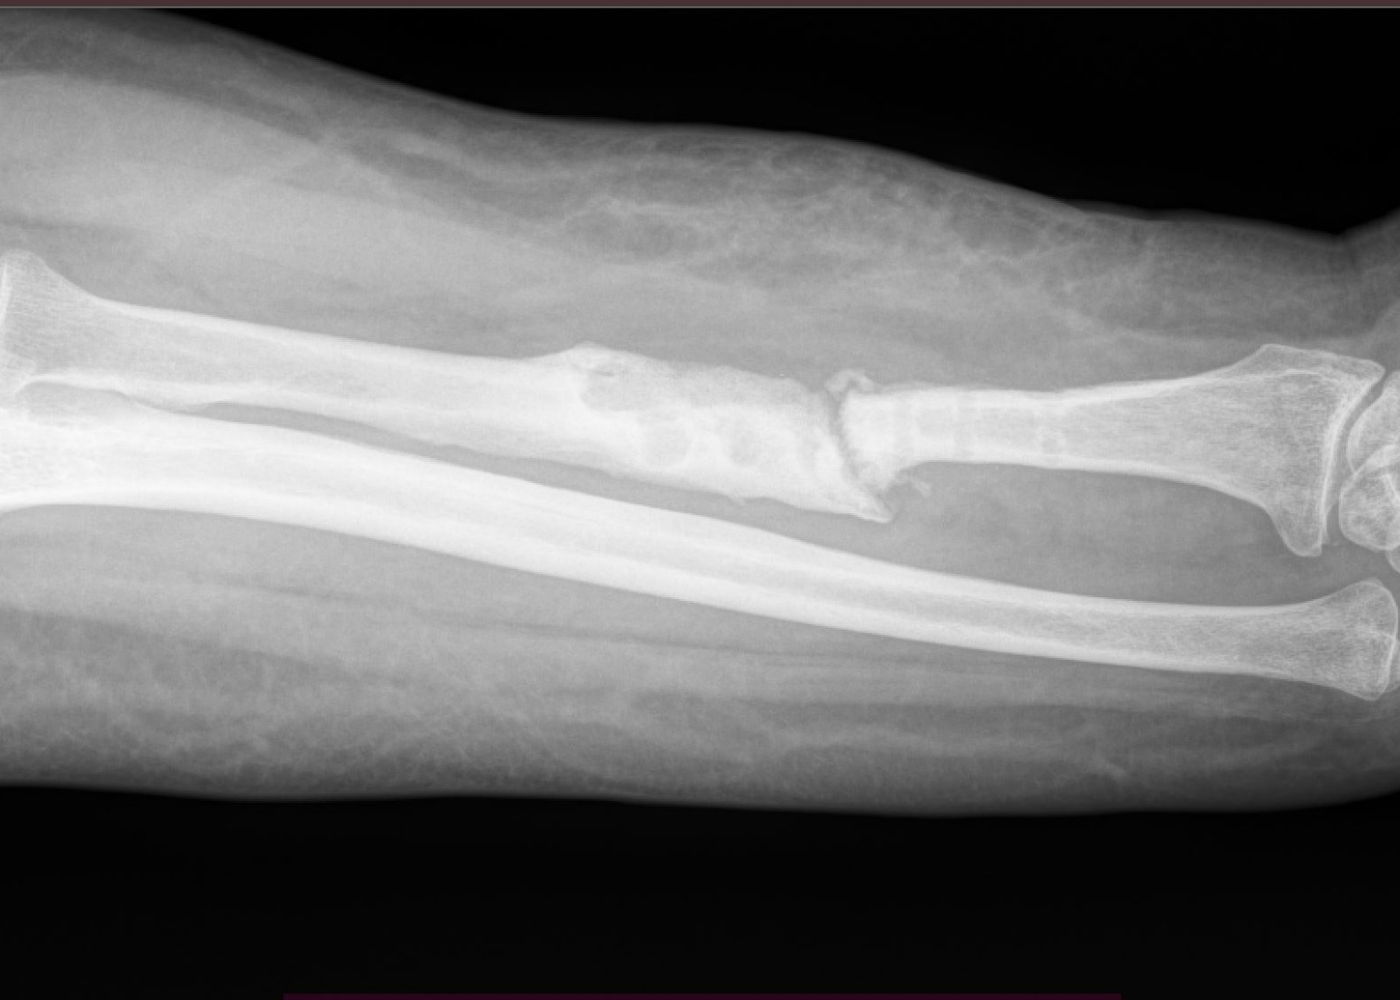

Հիվանդը նշել է, որ դեռևս 18 ամիս առաջ ընկնելու հետևանքով ստացել էր վնասվածք, կատարվել էր վիրահատություն՝ նախաբազկի ոսկրի մետաղական օստեոսինթեզ հարթակով և պտուտակներով։

Հետվիրահատական 2-րդ ամսում հարվածելու հետևանքով կրկնակի վնասել էր նախաբազուկը՝ առաջացնելով մետաղական կոնստրուկցիայի տեղաշարժ, ինչի կապակցությամբ ստացել էր կոնսերվատիվ բուժում՝ գիպսային վիրակապով։

Կատարված հետազոտությունների հիման վրա տղամարդու մոտ ախտորոշվել է ոսկրային դեֆեկտ, ոսկրի, մկանների, ջլերի և նախաբազուկի կարճացում, հոդի ֆունկցիայի խանգարում։ Բուժառուն հոսպիտալացվել է Վնասվածքաբանության և օրթոպեդիայի բաժանմունք՝ ստացիոնար բուժում ստանալու նպատակով։

Ձևավորվել է բժշկական թիմ՝ օրթոպեդիայի և վնասվածքաբանության բաժանմունքի, և պլաստիկ միկրովիրաբուժության բաժանմունքի բժիշկների մասնակցությամբ։ Մասնագետների առաջ բարդ խնդիր էր դրված՝ մի կողմում չսերտաճած կոտրվածքն էր՝ կեղծ հոդի առկայությամբ, ճաճանչային զարկերակի սպիացած վնասվածքով, մյուս կողմում՝ ոսկրային դեֆեկտի պատճառով նախաբազուկի կարճացումը, ձեռքի ֆունկցիայի կորուստը, ճաճանչ-դաստակային հոդի հնացած հոդախախտը։